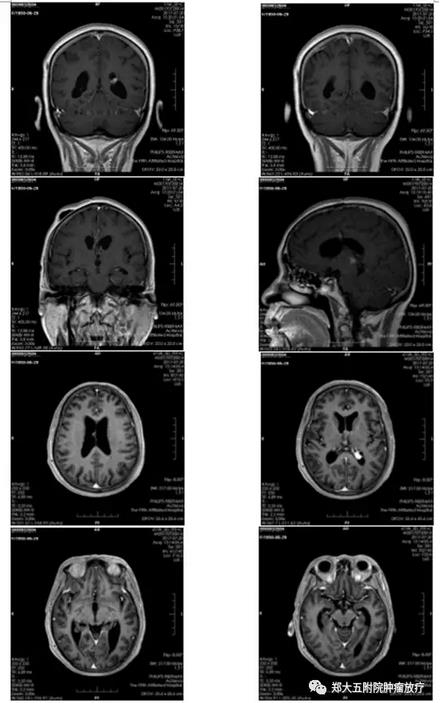

▲ 患者放疗后核磁共振图

王大妈的主管医师任振泰介绍:容积弧形调强放射治疗(VMAT)作为肿瘤治疗疗效好、周围正常组织损伤小的精准放射治疗技术很适合病人此阶段治疗。经过2周放射治疗后,病人意识逐渐恢复。3周复查头部核磁共振成像检查(MRI)提示肿块明显缩小。

放疗科巴楠主任介绍:“经过精准放疗后,病人颅内肿瘤缩小,由入院时的意识模糊到出院时的谈笑风生,这就是一名医生的幸福所在。去年科室引进医科达Synergy VMAT直线加速器、三维矩阵等剂量验证设备,能够很好地开展影像引导调强放疗IGRT、容积弧形调强放疗VMAT,为很多复杂疑难重症的肿瘤病人解除了病痛”。